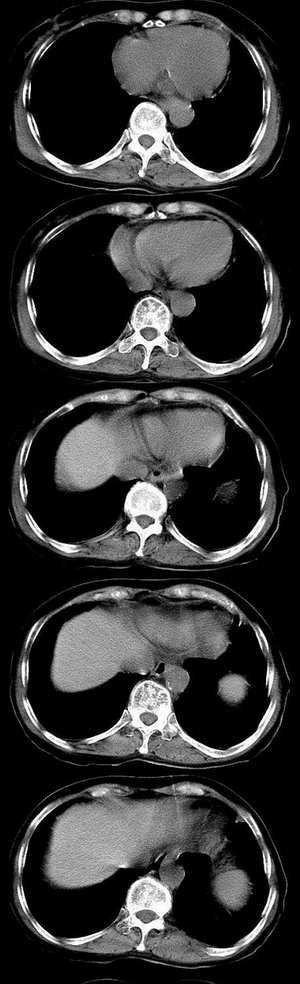

f73.反复胸痛、咳嗽5个月,加重1周入院。双肺呼吸音粗,闻及干湿性罗音。

右肺中叶炎症,肺气肿。抗炎后复查。

支持炎症,炎症纵隔淋巴结也可增大。建议短期抗炎后复查较为妥当。

慢支炎,肺部感染,非局限性间质纤维改变,舌段可疑支气管扩张。中叶病变肿瘤待排。